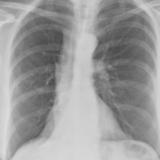

Lobar Collapse

LUL Collapse

LLL Collapse

RLL Collapse

RUL Collapse

RML Collapse